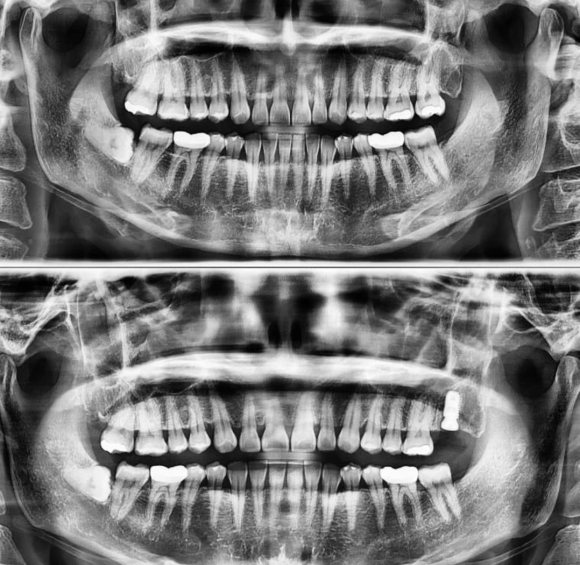

환자분 사진 상 오른쪽 위 치아의 뿌리 크랙으로 인항 극심한 증상으로

신경치료가 더 심한 통증을 유발시키는 경우로 발치를 하고

당일 임플란트 식립을 한 케이스 입니다.

뼈의 질과 양이 양호하였기 때문에

상악동 수술과 뼈이식을 하지 않은 케이스 입니다.